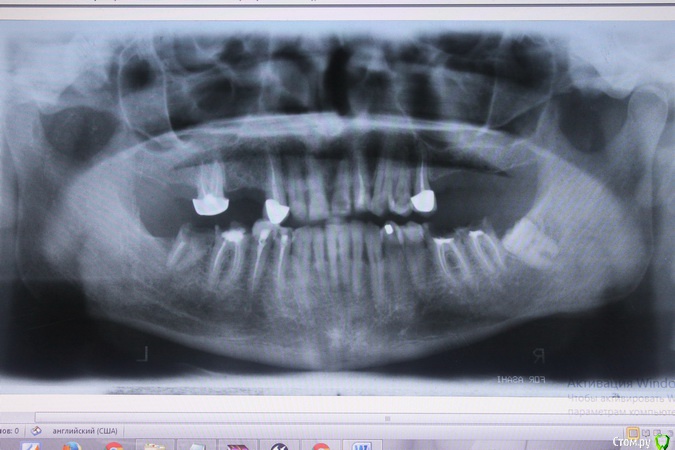

Доктор Добрых Дел Опубликовано 6 января, 2017 Поделиться Опубликовано 6 января, 2017 (изменено) Санация (лечение парадонтита, лечение кариеса, перелечивание каналовудаление разрушенных зубов и ретинированного 38), имплантация ( справа вверху и внизу по одному имплантату и слева вверху два) протезирование. Это естественно все очень условно и обобщенно, поскольку без осмотра полости рта и КЛКТ ничего более предметного Вам никто не скажет. Изменено 6 января, 2017 пользователем Доктор Добрых Дел Ссылка на комментарий

M@estro Опубликовано 8 января, 2017 Поделиться Опубликовано 8 января, 2017 Здравствуйте! У Вас комплексные проблемы с зубами, решать которые на расстоянии (Питер) - будет не очень комфортно для всех участников процесса. Рядом с Вашим местоположением большое количество адекватных докторов,которым можно доверить свое Здоровье. Судя по снимку, необходим комплексный план реабилитации, включающий подготовку ( терапевтическую и хирургическую ( удаления и имплантацию) - и протезирование. Ссылка на комментарий